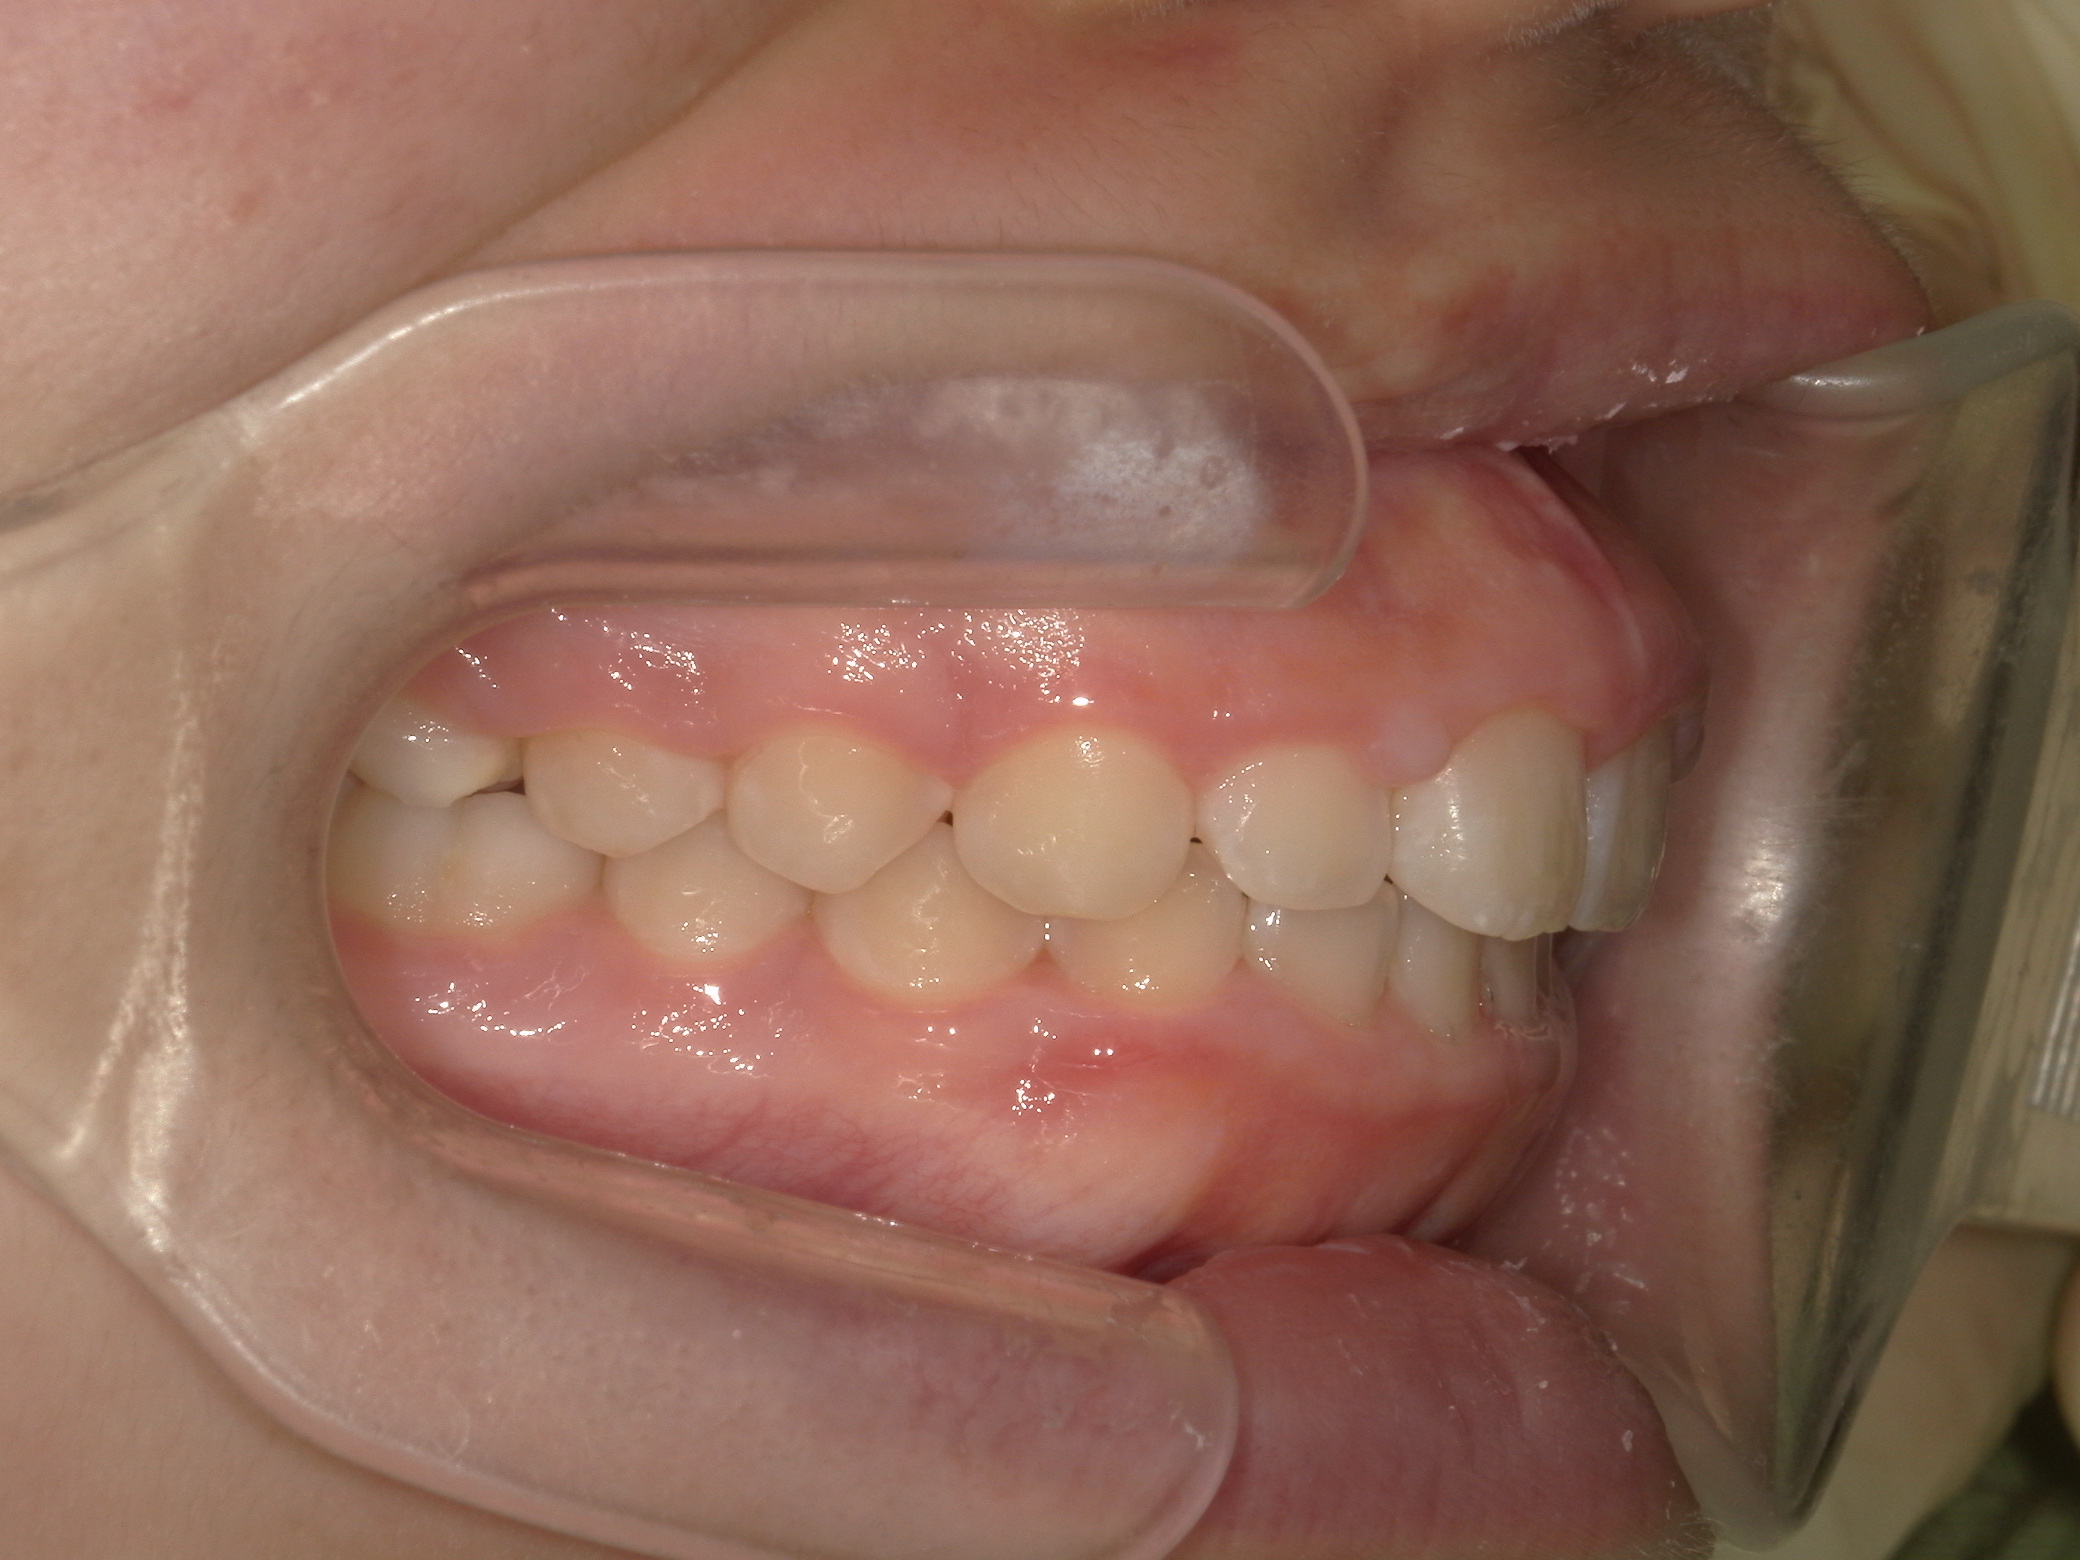

【中学生】インビザライン矯正 上顎前突(出っ歯)を改善

中学生以降

インビザライン フル

出っ歯

過蓋咬合

非抜歯

2期治療のみ

Before

After

治療期間

1.7年

治療開始

14歳歳

種類

インビザライン矯正

使用装置

インビザラインフル ディスキング併用

コメント

しっかり装着してくれて 予定通りに治療が終了しました。